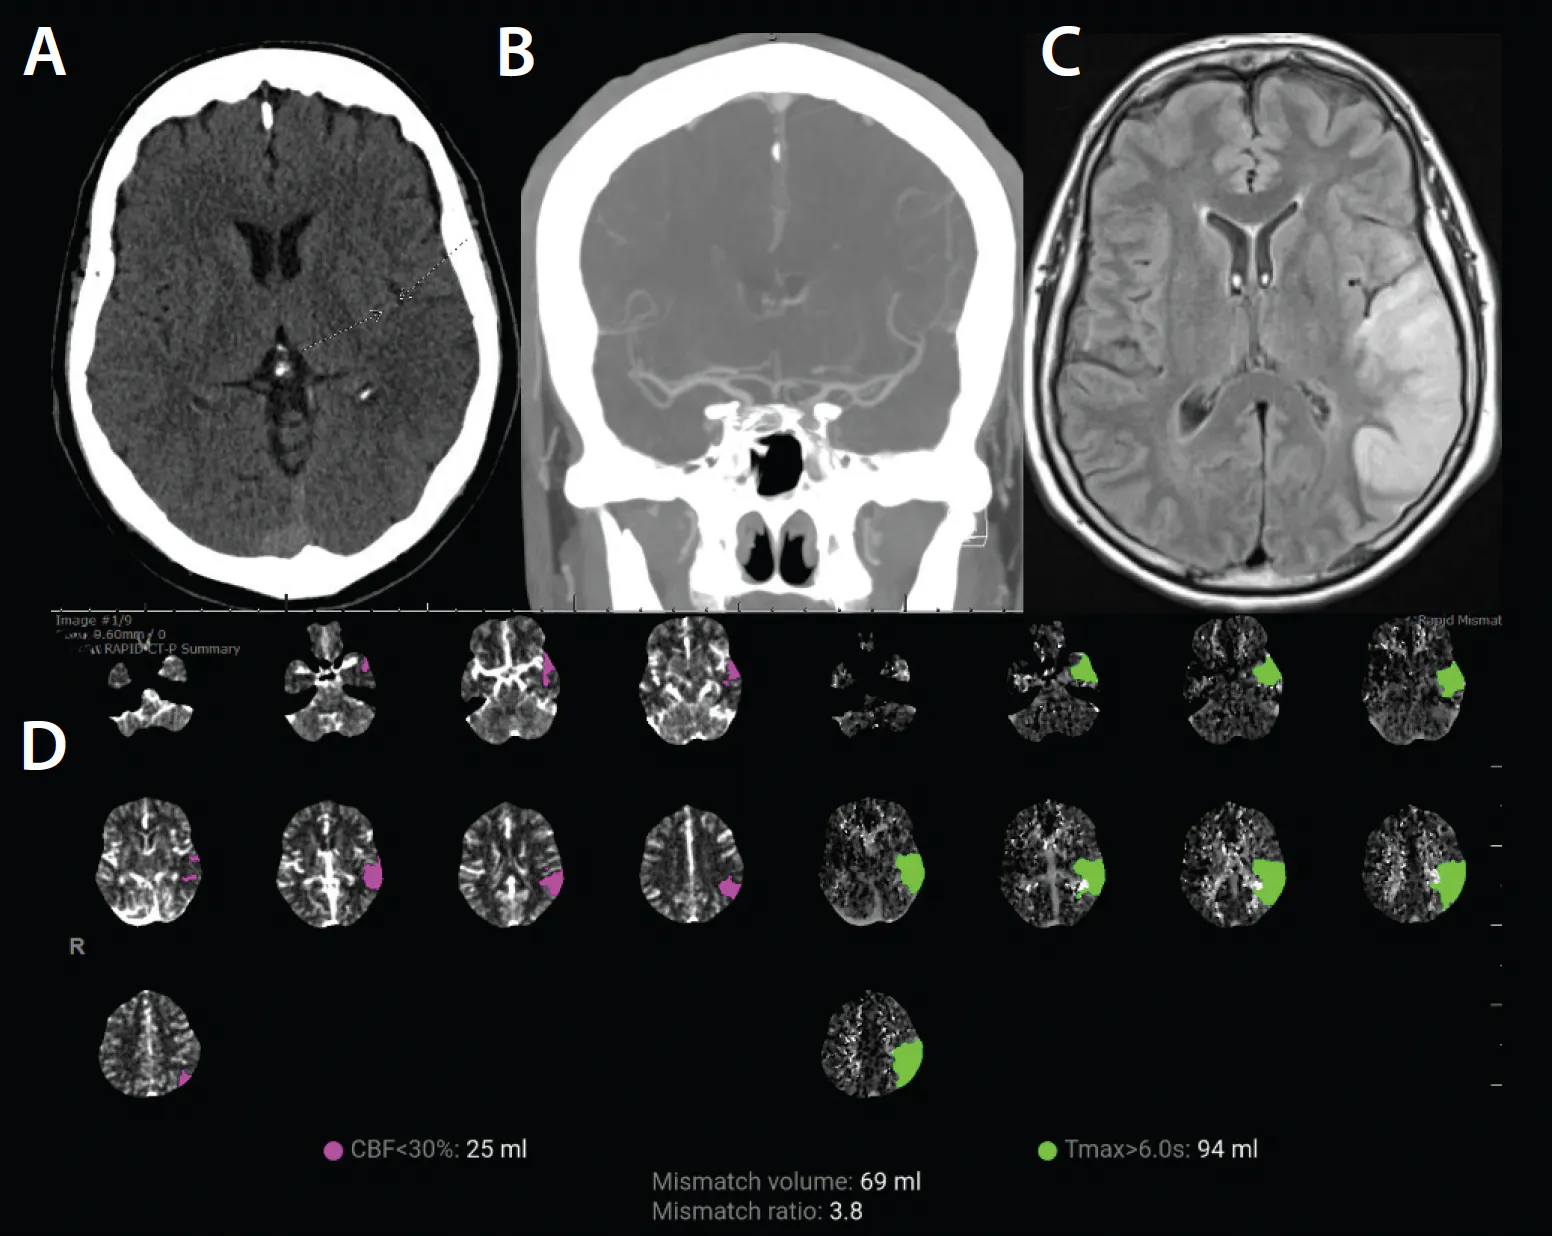

A man in his early 60s with prior carotid endarterectomy (CEA) followed by interposition common carotid artery (CCA)–to–internal carotid artery (ICA) bypass for recurrent disease presented. Despite smoking cessation initiatives and optimal drug therapy, the patient continued tobacco use and developed progressive severe restenosis within the bypass conduit several years later, which was identified on surveillance duplex ultrasound. The distal anastomosis demonstrated high-grade restenosis > 80% (Figure 1A), and the bypass developed intraluminal thickening suggestive of soft heterogeneous plaque morphology on ultrasound (Figure 1B).

Figure 1. Longitudinal view ultrasound of the distal anastomosis at the ICA bypass demonstrating severe focal plaque burden (A). Axial view ultrasound of the proximal CCA at the level of the clavicle with heterogeneous intimal thickening (B).